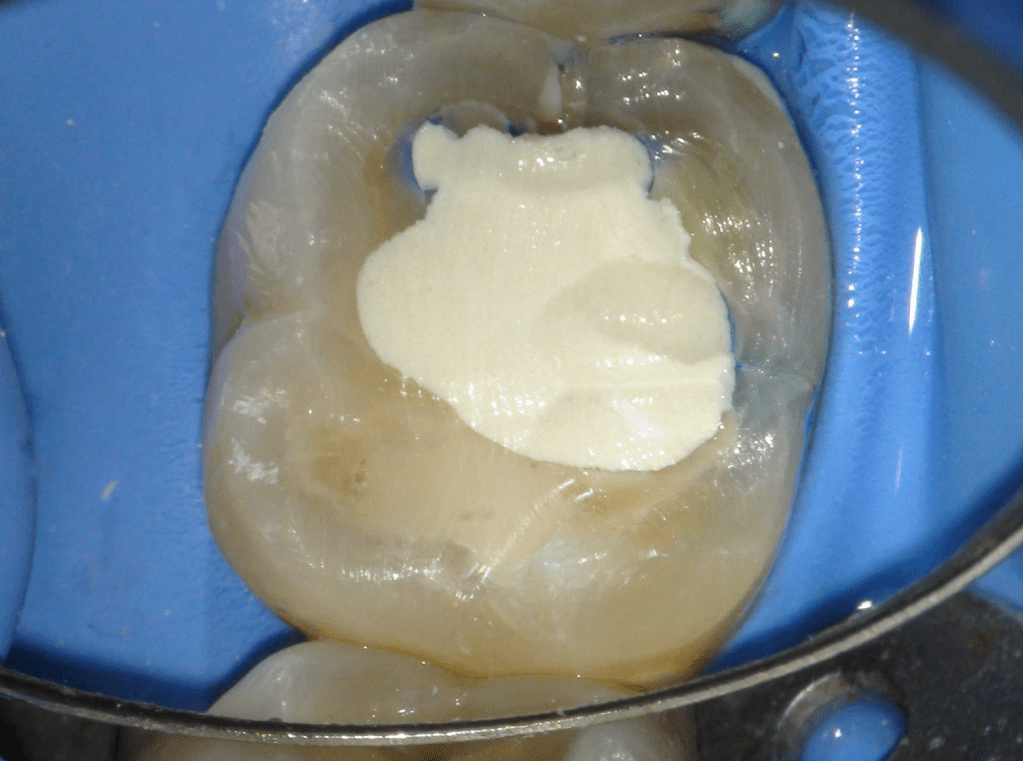

Pulpotomía biodentine + reco preendio